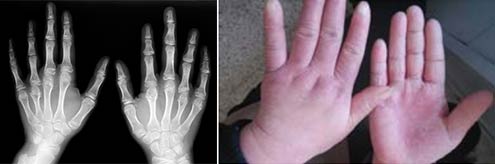

(图:治疗后,患者ct示关节肿胀尺偏症状消失)

3个疗程后:王女士基本恢复健康,关节处的疼痛消失,肿胀部位基本消退,手指、手腕、肘、膝盖等多部位受累情况明显好转,只需配合辅助疗法巩固治疗,调节体质机理平衡,增强自身的免疫力。

辅助治疗:经过机体免疫修复治疗,王女士各关节细胞免疫力、新陈代谢等均已恢复正常。手指等关节可自由弯曲,持重物也毫不费力,这让王女士感到非常欣慰。